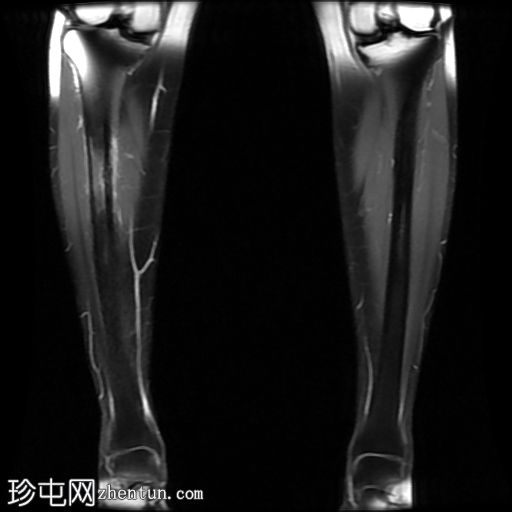

冠状位

T2加权像

内侧皮质可见一条低信号斜向皮质内线状影。

多发局灶性皮质内T2/STIR高信号病灶。皮质内可见一条线状信号异常区域。

邻近髓腔内广泛的骨髓水肿。

胫骨内侧缘骨膜水肿。